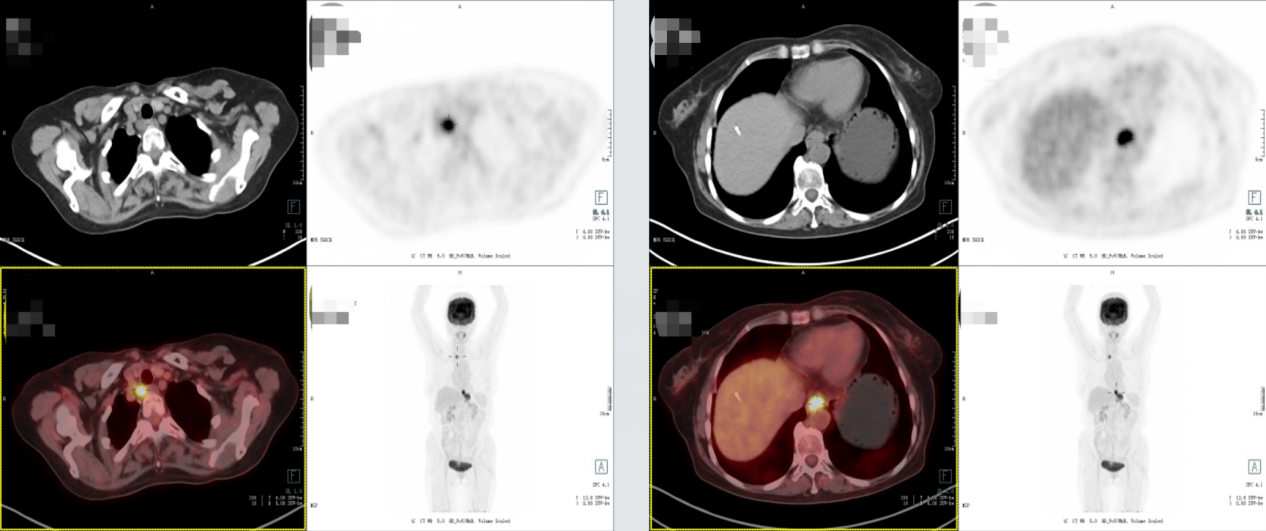

PET-CT:食管下段至贲门部软组织灶伴FDG代谢增高,考虑贲门癌累及食管下段。右侧胸廓入口处气管旁、贲门旁淋巴结转移。

2025年7月16日复查影像学显示,贲门癌化疗后,贲门胃壁稍增厚;双肺间质性改变。